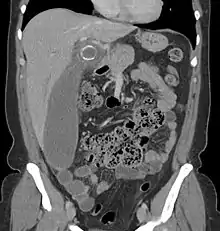

In children, the clinical examination is important to determine which children with abdominal pain should receive immediate surgical consultation and which should receive diagnostic imaging.[50] Because of the health risks of exposing children to radiation, ultrasound is the preferred first choice with CT scan being a legitimate follow-up if the ultrasound is inconclusive.[51][52][53] CT scan is more accurate than ultrasound for the diagnosis of appendicitis in adults and adolescents. CT scan has a sensitivity of 94%, specificity of 95%. Ultrasonography had an overall sensitivity of 86%, a specificity of 81%.[54]

Computed tomography

Where it is readily available, computed tomography (CT) has become frequently used, especially in people whose diagnosis is not obvious on history and physical examination. Although some concerns about interpretation are identified, a 2019 Cochrane review found that sensitivity and specificity of CT for the diagnosis of acute appendicitis in adults was high.[59] Concerns about radiation tend to limit use of CT in pregnant women and children, especially with the increasingly widespread usage of MRI.[60][61]

The accurate diagnosis of appendicitis is multi-tiered, with the size of the appendix having the strongest positive predictive value, while indirect features can either increase or decrease sensitivity and specificity. A size of over 6 mm is both 95% sensitive and specific for appendicitis.[62]

However, because the appendix can be filled with fecal material, causing intraluminal distention, this criterion has shown limited utility in more recent meta-analyses.[63] This is as opposed to ultrasound, in which the wall of the appendix can be more easily distinguished from intraluminal feces. In such scenarios, ancillary features such as increased wall enhancement as compared to adjacent bowel and inflammation of the surrounding fat, or fat stranding, can be supportive of the diagnosis. However, their absence does not preclude it. In severe cases with perforation, an adjacent phlegmon or abscess can be seen. Dense fluid layering in the pelvis can also result, related to either pus or enteric spillage. When patients are thin or younger, the relative absence of fat can make the appendix and surrounding fat stranding difficult to see.[63]